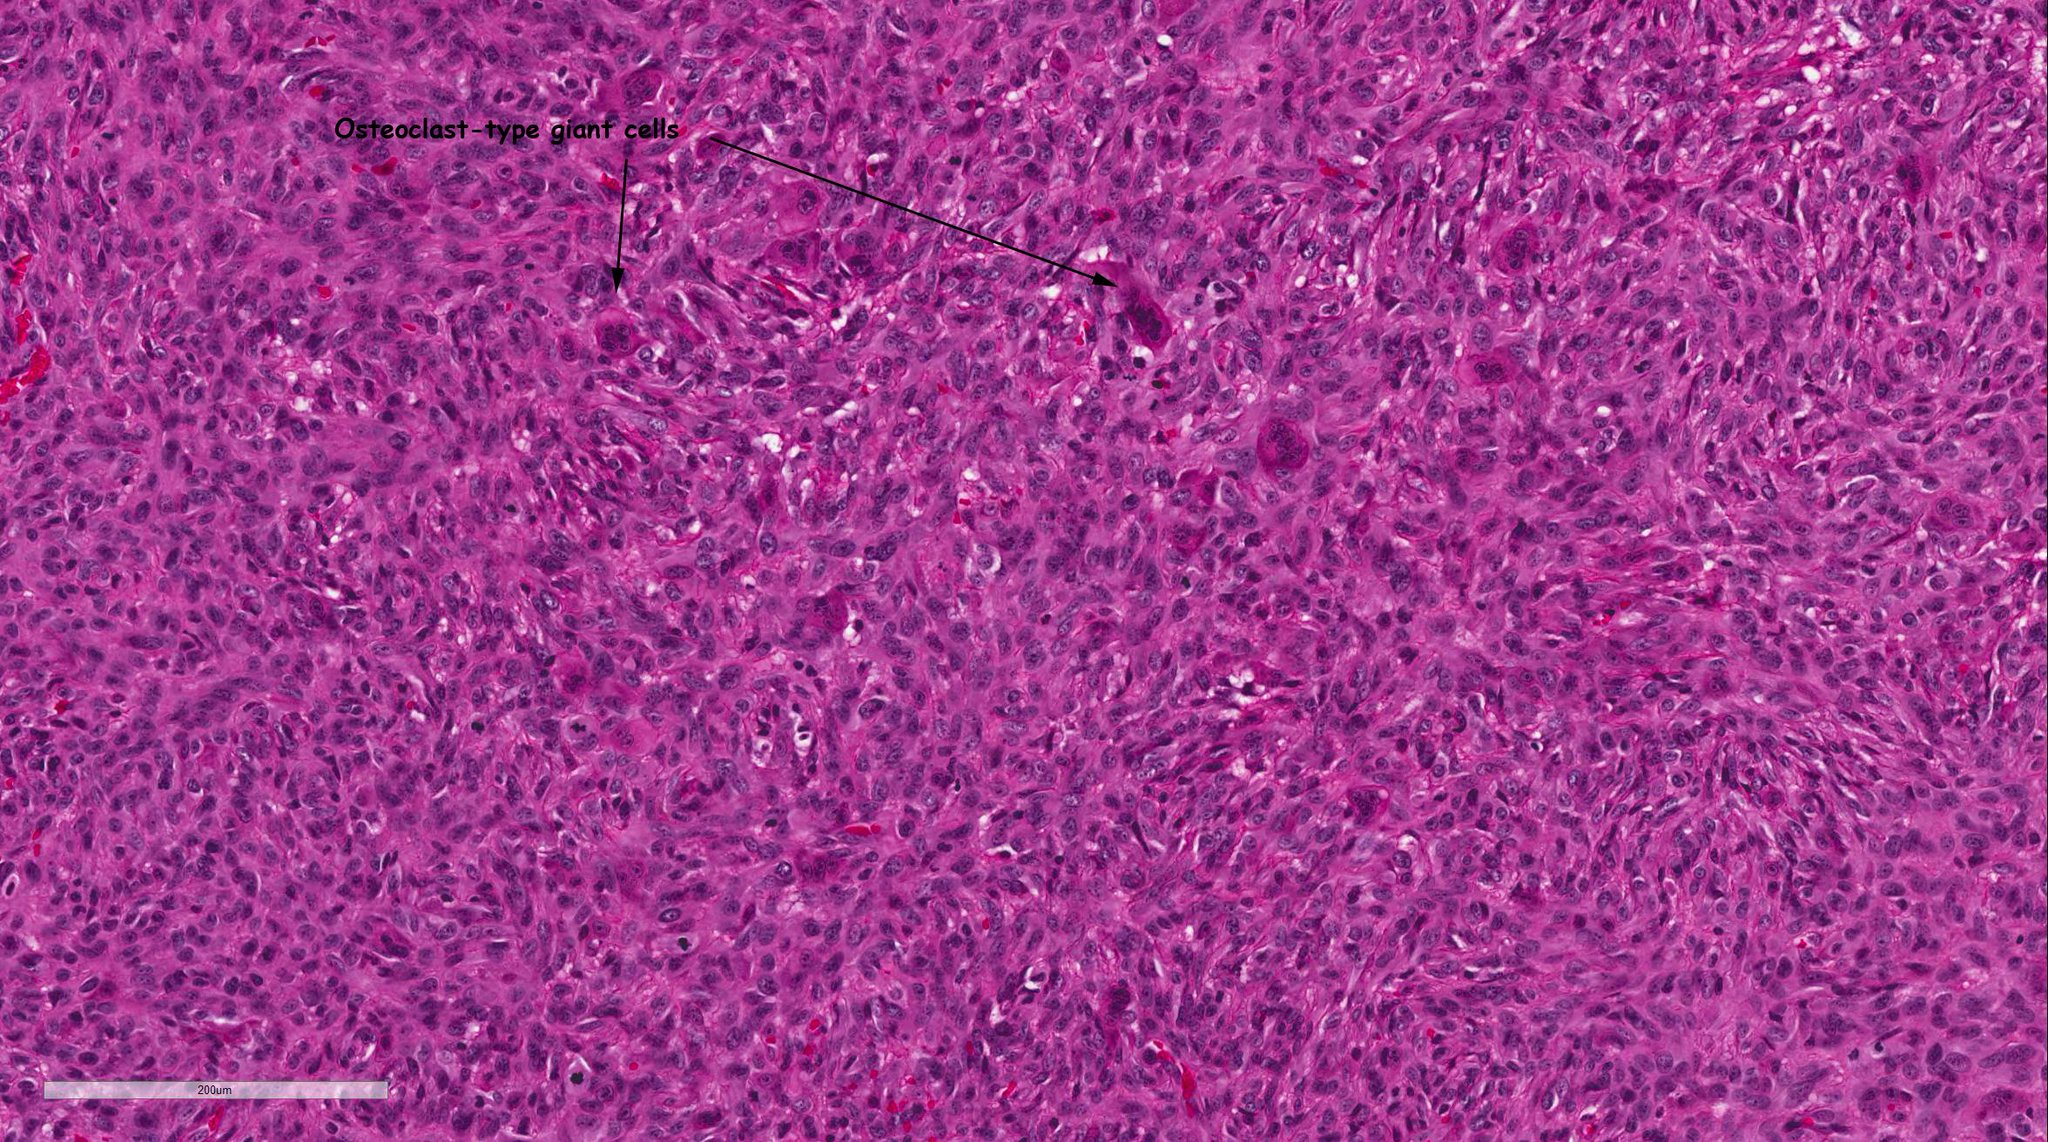

Bin Xu on Twitter "7 Heterologous component may be seen in a small Bin Xu Two Sigma Web hedge fund two sigma is dealing with fallout after a researcher who allegedly made unauthorized changes to his trading. I am a fifth year graduate student in the physics phd program and am working with prof. Previously, bin was a ph. Web bin xu is a quantitative researcher at two sigma investments based in new york city, new york.. Bin Xu Two Sigma.